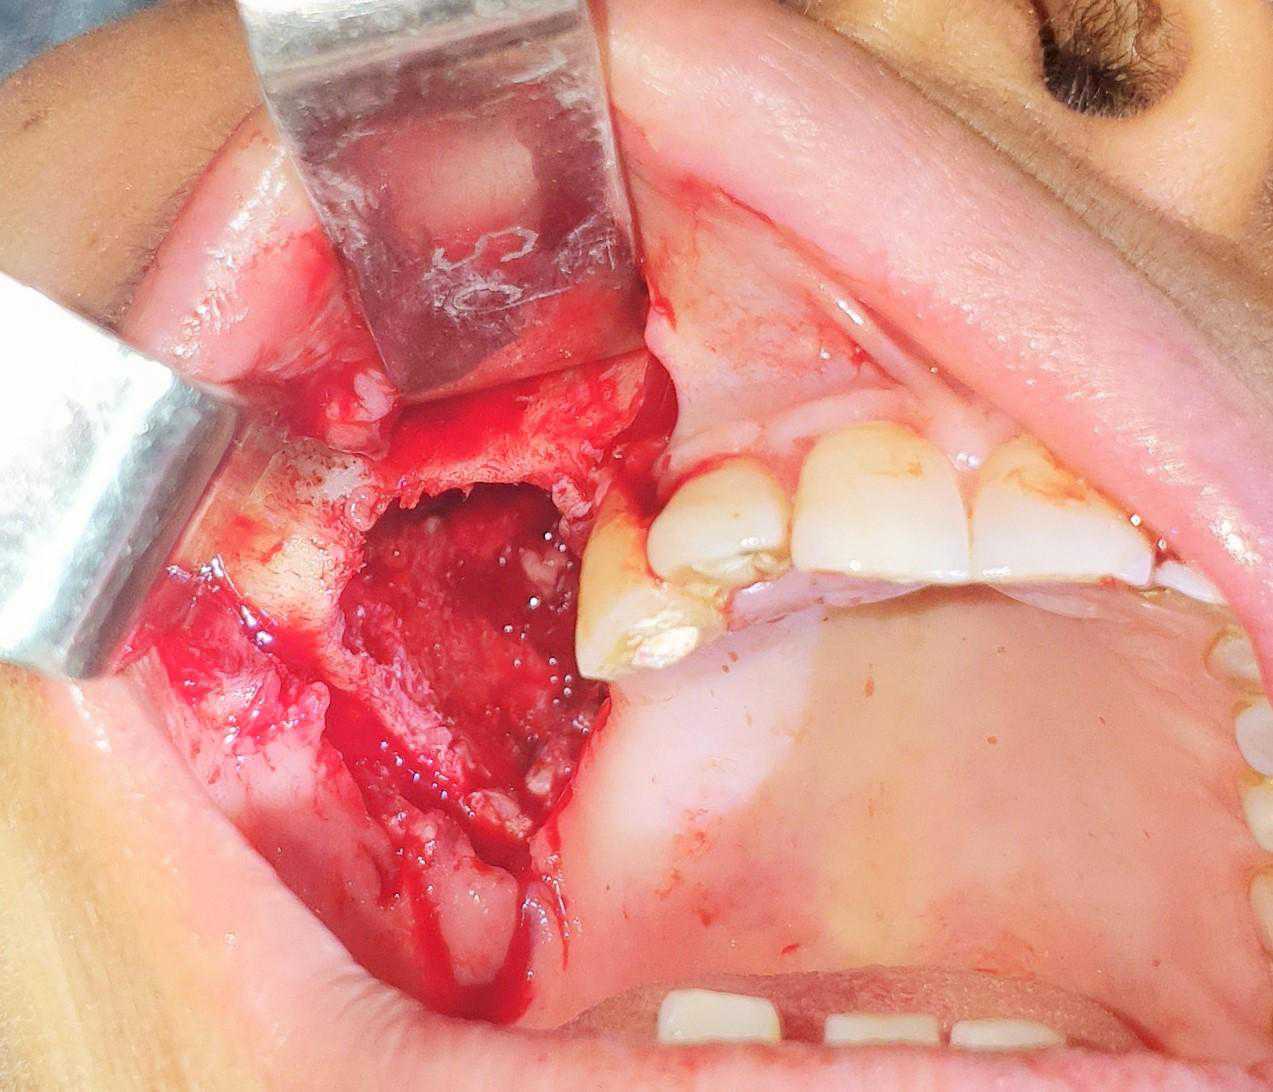

This is a case of Ameloblastic Fibro-Odontoma with a long term follow up.

https://demo.discussdentistry.com/forums/topic/post-mucormycosis-avascular-necrosis-of-maxilla-rehabilitation-with-zygomatic/#post-24499 <![CDATA[Post Mucormycosis Avascular necrosis of maxilla, rehabilitation with Zygomatic]]> https://demo.discussdentistry.com/forums/topic/post-mucormycosis-avascular-necrosis-of-maxilla-rehabilitation-with-zygomatic/#post-24499 Thu, 25 Aug 2022 12:14:40 +0000 Sankalp Mittal

• 20210604_101325 (2)20210604_101317 (2)20210604_103315 (2)20210604_102857 (2)20210604_104202 (2)20210604_104853 (2)20210824_105656 (2)20210824_112353 (2)20210824_114957 (2)20210824_131302 (2)20210826_100648 (2)20210826_100749 (2)20210826_100919 (2)20210914_183943 (2)20211001_17535220211012_18543620211012_192043 (2)20211012_185627 (2)20211012_195430 (3)20211027_193725 (2)20211027_200729 (2)20211027_200919